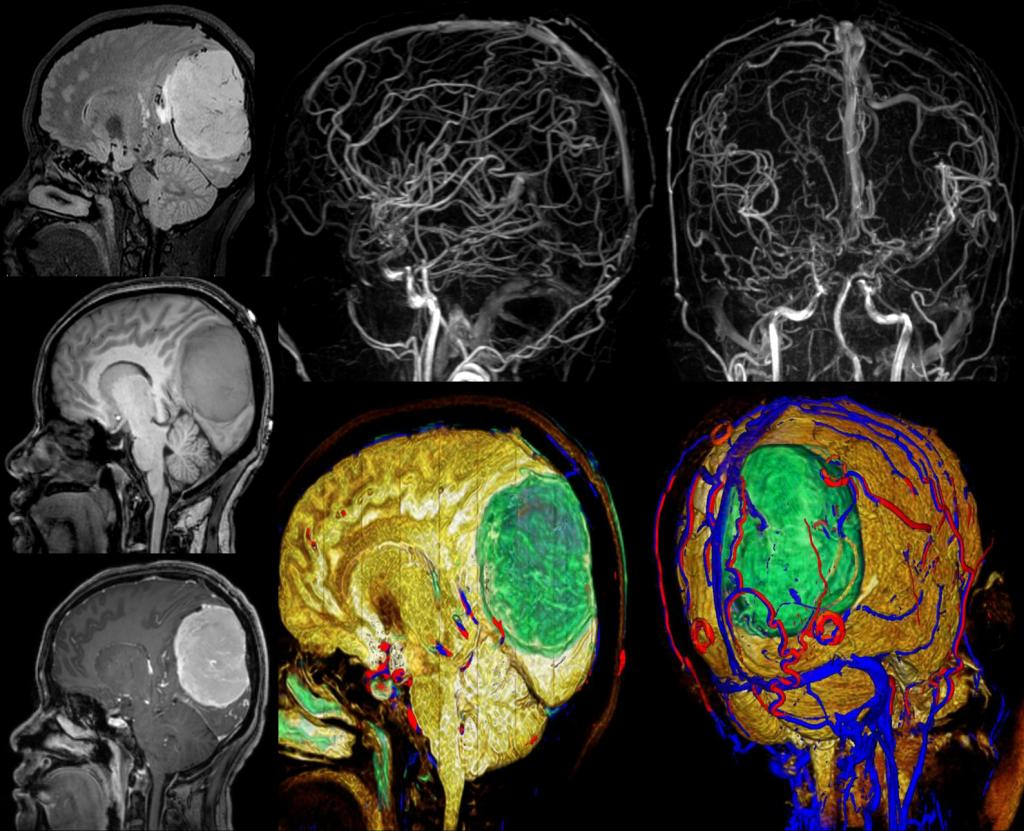

中心的研究团队包括多名医学影像领域的著名科学家和青年骨干,以医学成像和临床应用研究为核心,推动其在中国的发展,并在科技创新、产业结合方面提供多学科全球化的科研、教学和临床服务。影像中心拥有两台先进的3T全身磁共振成像系统(Philips Ingenia CX 3.0T和Siemens Prisma 3.0T),一台超高场5T全身磁共振成像系统(联影 Jupiter 5.0T),多套超声成像系统(含一台ICONEUS 脑功能超声成像系统),以及配套的成像技术、软硬件开发平台、图像数据处理工具和临床图像处理软件。中心的专业运行和技术支持团队以磁共振平台为核心,面向用户提供优秀的基础科学研究、成像技术研发和临床医学转化服务。

影像中心自成立以来,承担了科技部、国家自然科学基金委、卫生部、北京市科委等近百项国家和省部级项目,收到各种研究经费支持达5000万余元,已发表论文600余篇,发明专利60余项,国际专利10余项,培养学生130余人,获得各种奖励30余项。影像中心已成为全球重要的医学影像尤其是磁共振技术研发中心,开发出大视野高分辨血管壁多对比度成像、三维心肌定量成像、定量血流成像、定量生理成像、无变形高分辨率弥散成像等诸多原创技术,同时这些技术被广泛地应用在多项大规模临床人群队列研究当中形成了针对心脑血管、神经变性性疾病等原创性影像学解决方案。